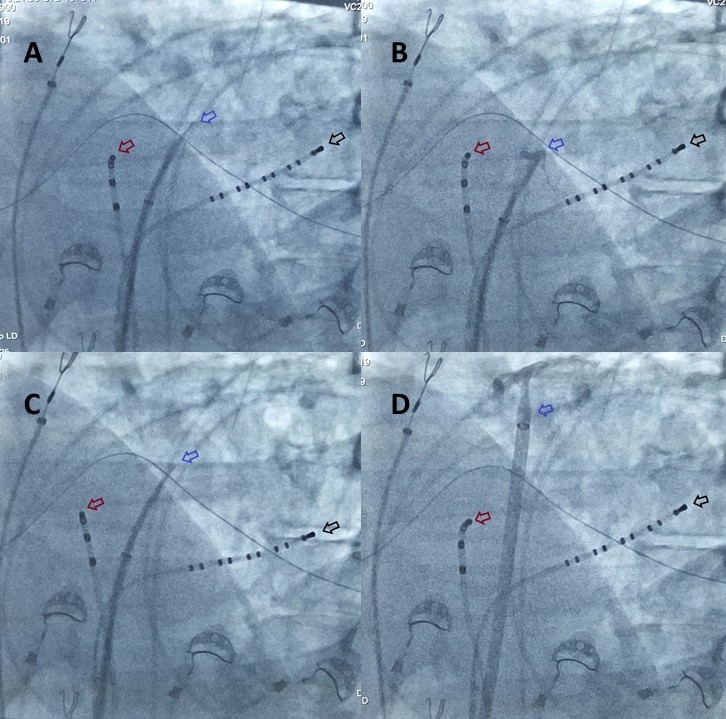

La punción transeptal es un procediento seguro y generalizado para el diagnóstico y tratamiento de las arritmias cardiacas localizadas en las cavidades izquierdas del corazón. En este artículo se describe la técnica con dos electrodos de registro intracavitario como referencia anatómica a partir de la experiencia inicial de los primeros doce casos.